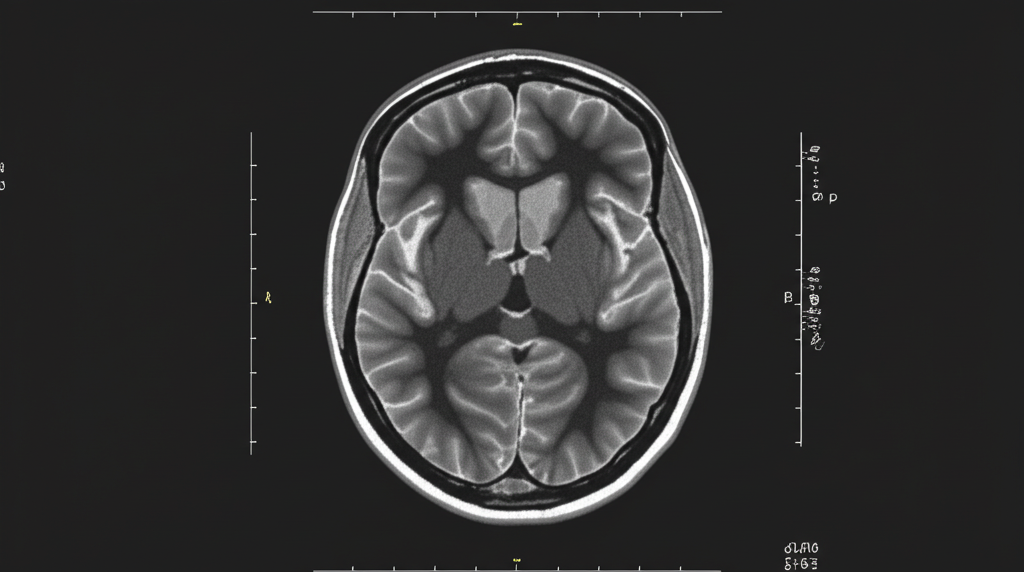

A ressonância magnética do crânio se destaca por sua capacidade de criar imagens detalhadas do cérebro e estruturas adjacentes. Essa técnica permite aos médicos visualizar o cérebro em diferentes ângulos. Com essas imagens, é possível identificar uma variedade de condições, desde tumores e aneurismas até esclerose múltipla e os efeitos de um acidente vascular cerebral. É como ter um mapa detalhado do seu cérebro!

Ilustração detalhada sobre ressonancia magnetica cranio: guia completo com dicas e técnicas essenciais para resultados eficientes